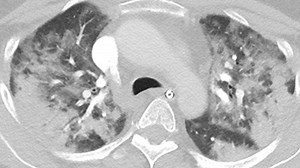

- Covid Lungs

CT Scan